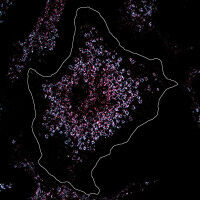

Biowissenschaften - Gesundheit - 04.12.2023

Proteintröpfchen zeigen neue Wege zur Hemmung von Transkriptionsfaktoren bei einer aggressiven Form von Prostatakrebs Viele menschliche Krebsgene gehören zur Gruppe der Transkriptionsfaktoren. Ein internationales Forscherteam vom Max-Planck-Institut für molekulare Genetik, dem Institute for Research in Biomedicine (Barcelona) und der University of British Columbia (Vancouver) hat nun einen möglichen Angriffspunkt gegen den Androgenrezeptor gefunden, den wichtigsten onkogenen Transkriptionsfaktor bei Prostatakrebs.